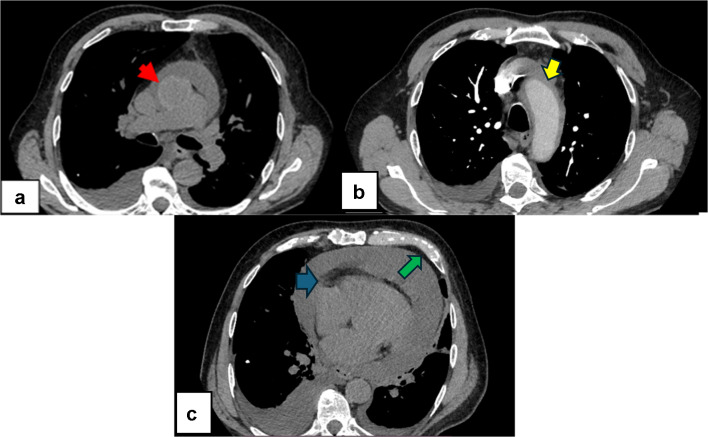

Systemic lupus erythematosus (SLE) is a chronic autoimmune disorder with diverse clinical manifestations. While small vessel vasculitis is a common SLE complication, lupus aortitis is an exceedingly rare entity with limited documentation. Here, we report a novel case of lupus aortitis misleadingly appearing on imaging studies as an aortic intramural hematoma in a 68-year-old male. The patient initially exhibited fatigue, dyspnea, and pericardial effusion. Imaging studies suggested an intramural hematoma of the ascending aorta and the aortic arch, prompting urgent surgical exploration. Intraoperative findings revealed a thickened, fibrotic, and heavily calcified aorta (egg-shell aorta) without hematoma. Subsequent histopathological and immunological analyses confirmed lupus aortitis. This case underscores the diagnostic challenges posed by this rare SLE complication, which can mimic other aortic pathologies. Early recognition and individualized treatment are paramount. Further studies are needed to elucidate its pathophysiology and establish standardized management guidelines.